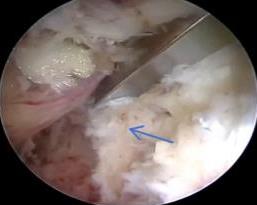

• 单侧双通道内镜下椎间盘切除术治疗钙化型腰椎间盘突出症的临床疗效分析

摘要:目的 观察单侧双通道内镜(UBE)下椎间盘切除术治疗钙化型腰椎间盘突出症(CLDH)的临床疗效。方法 回顾性分析2020年1月-2022年1月在该院行UBE下腰椎间盘切除术的25例单节段CLDH患者的临床资料。记录手术时间、术后住院时间和术后并发症情况。采用腰腿痛视觉模拟评分法(VAS)评分、腰椎日本骨科协会(JOA)评分和Oswestry功能障碍指数(ODI),评估术前、术后3 d、术后1个月和末次随访的临床疗效。末次随访时,采用改良Macnab标准,评估优良率。结果 术后随访12~24个月,平均(15.60±2.60)个月。手术时间为(58.67±10.73)min,术后住院时间为(4.65±0.63)d。术后3 d、术后1个月和末次随访时的VAS评分和ODI明显低于术前,JOA评分明显高于术前,差异均有统计学意义(P < 0.05)。末次随访时,根据改良的Macnab标准,15例为优,9例为良,1例为可,优良率为96.00%(24/25)。术后并发症:1例神经根腹侧硬膜囊撕裂,长度约5 mm,未行硬膜囊修补术,术后嘱患者卧床5 d,给予补液治疗,患者下床活动未诉头痛等不适,术后MRI显示:未见硬膜外大量积液;1例出现下肢感觉障碍,给予营养神经药物对症治疗,术后1个月随访时恢复。术后影像学检查显示:游离钙化组织基本被完全切除,神经根得到充分减压。末次随访时,未发现复发病例。结论 UBE下腰椎间盘切除术治疗CLDH安全、有效,值得应用于临床。